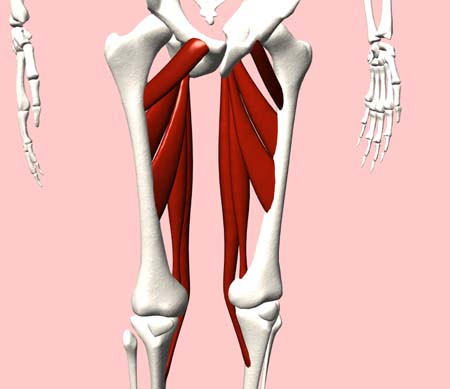

太ももの内側には、大内転筋、長内転筋などの股関節内転筋群という筋肉群があります。内転筋は股関節を内転させる、股を閉じる動きに関わる筋肉で、3層の筋肉層によって構成されています。

第1層(表層)は恥骨筋・薄筋・長内転筋の3つの筋肉があります。第2層(中間層)には短内転筋があります。第3層(深層)には大内転筋・小内転筋があります。これら3つの筋肉を内転筋群と言います。内転筋群に痛みを感じた場合、炎症を起こしている状態は内転筋群炎症になります。